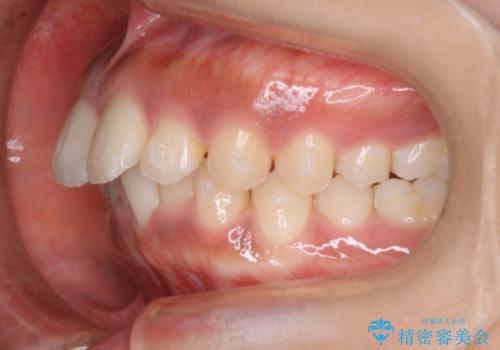

インビザライン矯正 歯を抜かずに出っ歯を改善!

- 出っ歯と前歯の隙間が空いていることを気にされて来院されました。

また、自然な感じで口元を下げていとのことでした。

奥歯のかみ合わせが問題なかったため、上顎の前歯の隙間を閉じるとともに、上顎の歯の側面を削ることをメインにして、出っ歯を改善する治療計画としました。

上顎の歯の傾きを変えるうえで、下顎の歯とのバランスのことも考え、下顎の歯の側面も削ることを加えています。

また、今回は口元を変えたい中に、劇的な変化は避けたいとのことだったので、抜歯をしない計画としています。

抜歯をしない場合、口元の変化は感じにくいですが、前歯の傾きが変わることで、口の閉じやすさは感じていただけたとのことです。

症例にもよりますが、本症例は奥歯のかみ合わせに問題がなかったので歯の側面を削ることメインに、前歯の傾きを改善することができました。

抜歯を行う場合や抜歯をしなくても奥歯の位置をずらす場合は、治療期間が長期化することが多いですが、今回は歯を削ることで改善できたため、短期間で治療を完了することができました。